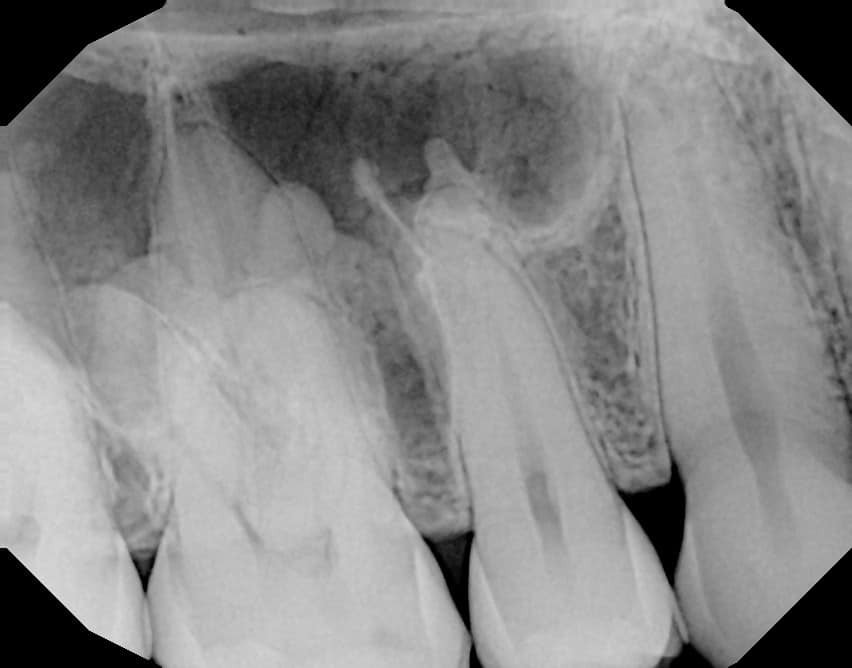

Dense Bone Island

Also known as idiopathic osteosclerosis, enostosis, or hyperostosis, this finding is of unknown etiology and typically occurs in the posterior mandible. While often associated with the root apices of mandibular molars and premolars, it can be found anywhere within the jaws.

Dense bone islands present as a dense, homogenous radiopacity with an amorphous shape. When associated with a root, a regular PDL space is maintained and the tooth is vital. On a CBCT, it will blend into adjacent cortices with no thinning or expansion. These features help differentiate idiopathic osteosclerosis from similar entities such as condensing osteitis, cemento-osseous dysplasia, hypercementosis, and cementoblastoma.

No treatment is necessary for areas of idiopathic osteosclerosis.

Dense Bone Island (Diagnostic Imaging Oral and Maxillofacial - Lisa Koenig)